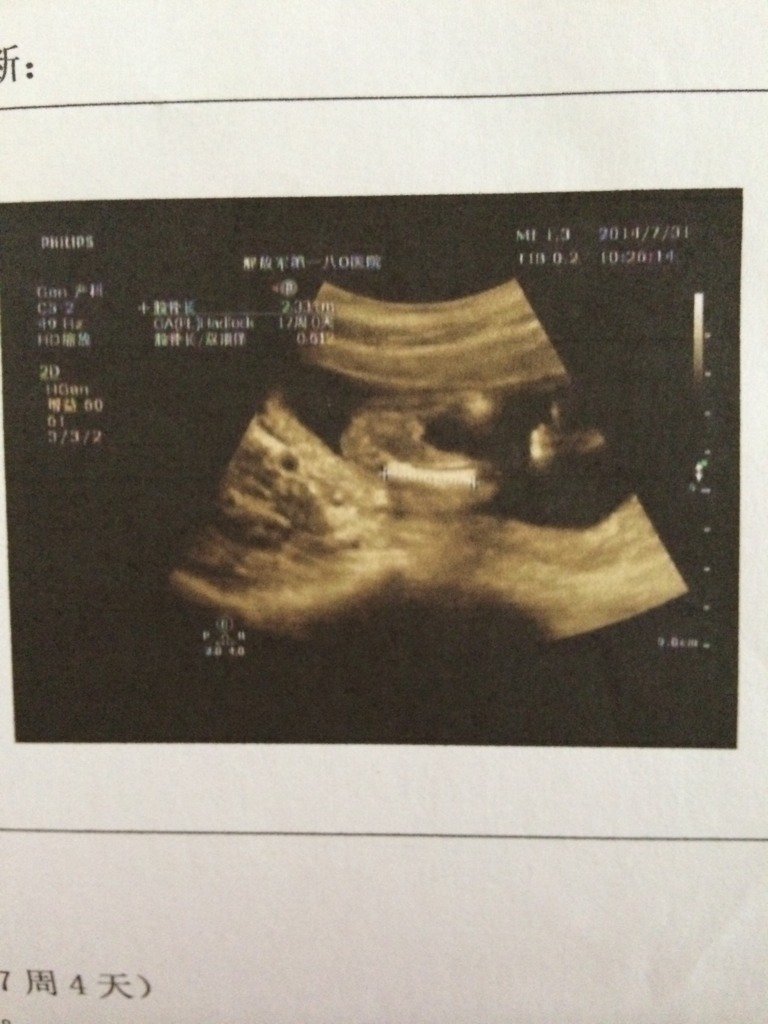

17+4做的彩超 哪位大神帮忙看看这是男宝还是女宝 17+4做的彩超 哪位大神帮忙看看这是男宝还是女宝🙏 点击展开 yaniki_yk 2020-02-17 06:24 为您推荐: 其他回答 你好:胎儿性别是从彩超报告单上是看不出来的。 一般来讲非医学必要是不允许是鉴定胎儿的性别的,是违反法律和医院的规定的。 虽然用彩超可以大致的观察出来男女,但是彩超报告单上的照片是不会拍到能辨别男女的图片的。 19342988 2020-10-18 02:31 相关问题 有哪位宝妈能看懂这个彩超单呢,请帮忙看看是男宝还是女宝 灵武孕妈妈都是在哪里做的四维彩超?求大神帮助 怀孕的妈妈们有没有拍过四维彩超的呀?大神们帮帮忙